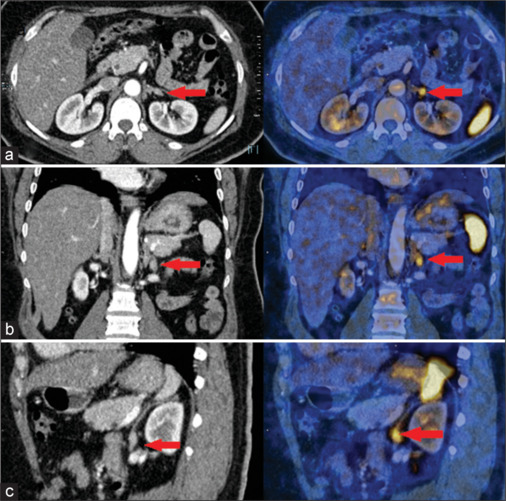

原发性醛固酮增多症(Primary aldosteronism, PA)是继发性高血压的常见病因之一,其特点是醛固酮自主分泌过多,同时肾素抑制。通过手术治疗的PA患者的临床和生化缓解率远高于通过药物治疗的患者;因此,亚型PA对于确定哪些患者将从手术中获益最大至关重要。计算机断层扫描(CT)扫描与肾上腺协议和肾上腺静脉采样(AVS)是常用的PA亚型分类。CT扫描是结构成像,不能提供功能信息,而AVS是一种侵入性的、技术上具有挑战性的方法,成功率有限,并发症风险高。C-X-C趋化因子受体4型(CXCR4)在醛固酮产生组织中过表达,但在无功能腺瘤中的表达几乎可以忽略不计。正电子发射断层扫描示踪剂68ga - pentxafor是CXCR4的特异性配体,可无创检测醛固酮产生性腺瘤,指导手术治疗。下面的图像系列展示了ga -68- pentxafor对PA亚型诊断的效用和结果模式。

Primary aldosteronism (PA) is one of the prevalent causes of secondary hypertension, characterized by the autonomous hypersecretion of aldosterone and concurrent renin inhibition. Clinical and biochemical remission rates for patients with PA achieved through surgery are far higher compared to those achieved through drug treatment; hence, subtyping PA is crucial for identifying patients who will benefit most from surgery. Computed tomography (CT) scan with adrenal protocol and adrenal venous sampling (AVS) is used conventionally for PA subtype classification. CT scans, being structural imaging, cannot provide functional information, while AVS is an invasive, technically challenging method with a limited success rate and a high risk of complications. The C-X-C chemokine receptor type 4 (CXCR4) is overexpressed in aldosterone-producing tissue but is almost negligibly expressed in nonfunctional adenoma. The positron emission tomography tracer 68Ga-pentixafor, a specific ligand for CXCR4, can detect aldosterone-producing adenoma noninvasively, which can guide surgical treatment. The image series below demonstrates the utility and patterns of findings on Ga-68-pentixafor for subtyping PA.